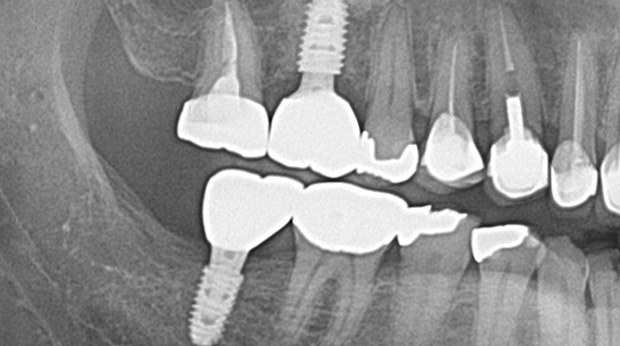

의식하진정법(수면마취)/임플란트

임플란트와 사랑니 발치는 외과적 시술로 잇몸을 절개하는 외과적 시술은

짧으면 짧을 수록 시술 후 붓기와 통증이 최소화됩니다.

치과의사 경력 14년차 구강외과 전문의가 빠르고 안전하게, 아프지 않게 수술해 드립니다.